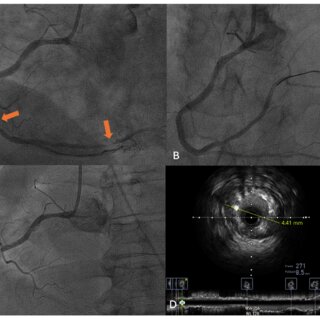

Angioplasty is a procedure to open narrowed or blocked blood vessels. An interventional radiologist guides a small balloon-tipped catheter to the site of the blockage, and then the balloon is inflated. While the balloon compresses the plaque against the artery wall, it widens the vessel to restore blood flow. Surgeons sometimes place stents inside the body to keep the vessel open.